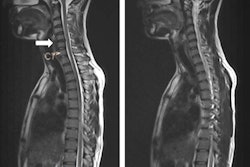

Full-spine radiography remains the gold standard for identifying and monitoring scoliosis, defined as lateral curvature of the spine, according to lead author Dr. Caroline Ernst, from the department of radiology at Universitair Ziekenhuis Brussel (UZ Brussel) in Brussels. The condition occurs in between 2% and 4% of children 6 to 14 years of age, and imaging is required to help determine treatment by characterizing the type of curve and its severity, identify possible underlying pathologies, and detect any increase in deformation.

"Scoliosis patients typically receive multiple radiographs during treatment and follow-up," the authors noted in an e-poster presentation at ECR 2016 in Vienna. "Average numbers of 22.9 radiographs per patient are reported in the literature. Owing to the increased radiation sensitivity of children and the numerous follow-up images with exposure of the most sensitive organs (thyroid gland, mammary gland, and gonads), radiation safety is of particular concern in patients with scoliosis."